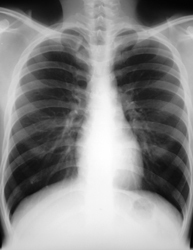

Malheureusement, un an plus tard, le PSA est dosé à 93,2 ng/mL alors que la testostéronémie est indosable. La scintigraphie met en évidence l’aspect suivant :

Figure 1 (Source : Matthieu Roulleaux Dugage)

L’IRM rachidienne confirme l’atteinte métastatique diffuse, mais il n’existe pas de signe de compression médullaire.